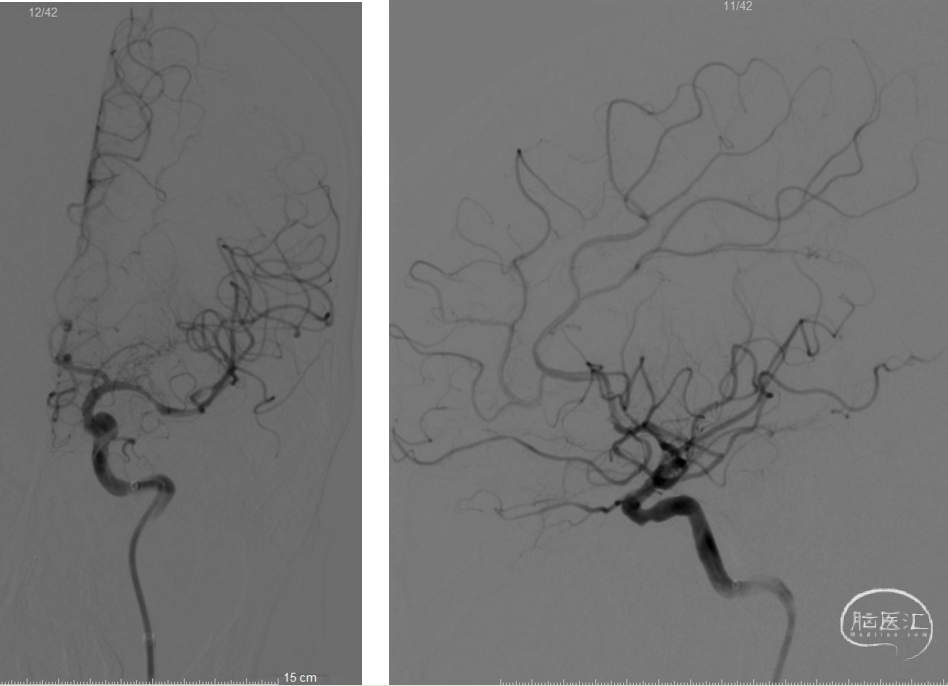

再次给予Gateway球囊以6ATM压力缓慢扩张,并缓慢注射替罗非班5ml,观察20分钟,M1处血管毛糙,血管回弹明显,给予经微导管释放Neuroform Atlas 4.0mm×21mm支架满意。复查造影左侧大脑中动脉及大脑前动脉显影良好,mTICI3级,观察10分钟后,再次复查造影左侧大脑中动脉及大脑前动脉显影良好。行Dyna CT见未见明显出血灶。

术后左颈内正侧位